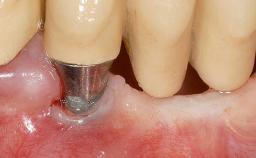

Soft-Tissue Volume Augmentation Using a Connective-Tissue Graft Harvested from the Maxillary Tuberosity

In 1983, a 51-year-old non-smoking patient was referred for the treatment of moderate chronic periodontitis. At the initial examination, 47% of sites exhibited probing depths of 4 to 6 mm. Periodontal therapy consisted of initial periodontal treatment including oral-hygiene instructions and supra- and subgingival debridement, followed by periodontal surgery to eliminate residual pockets.